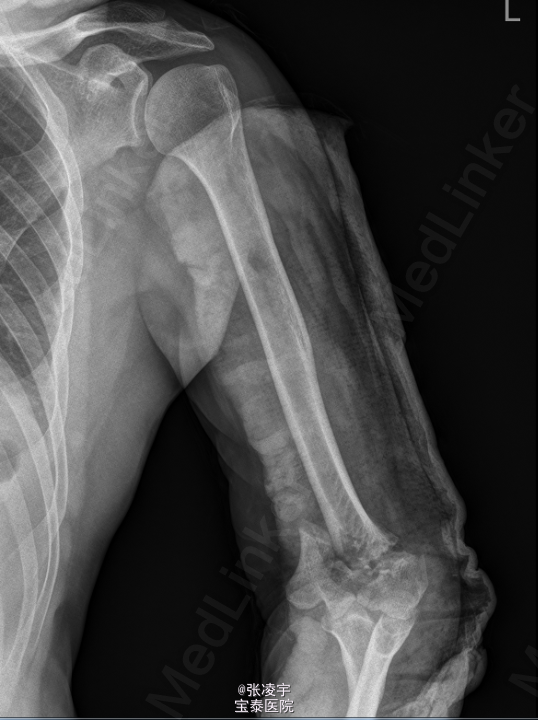

男,53岁,因“ 摔倒致双上肢疼痛5小时”于入院。 患者于5小时前从1米高处摔落,双上肢着地,伤后即感左右肘关节疼痛,伴左肘关节出血、鼻出血,至当地医院就诊。

右上肢伸直受限,感觉无异常,左上肢石膏敷料固定,未见明显渗血渗液,双下肢活动自如,肌力V级,病理征阴性。X线:左侧肱骨骨折。

初步诊断: 1.左肱骨开放性骨折,右肘关节脱位? 行左肘关节韧带修补外固定架固定 。